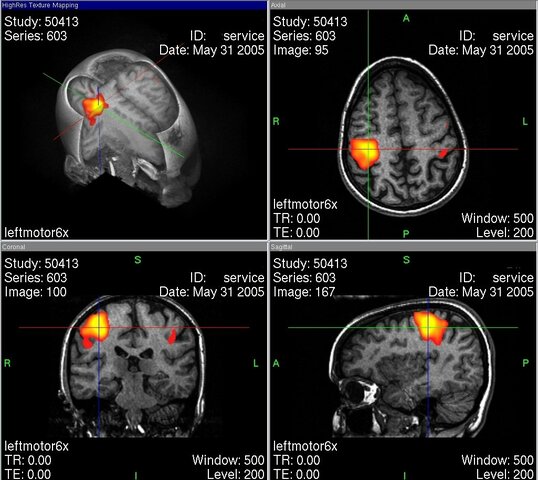

• fRNM cerebral - Seiji Ogawa

fRNM cerebral - Seiji Ogawa

Ogawa aplica las técnicas de RNM para registrar la actividad cerebral dando origen a la Resonancia Nuclear Magnética Funcional, una de las técnicas más útiles y más usadas hoy en día para el estudio del cerebro. Referencia: Casierra, Y., Pinilla, A., & Rentería, A.(2017) Usos actuales de la resonancia nuclear magnética funcional, Revista Salud Areandina. 31-46. 2017-1

Imagen: M.R.W.HH de Wikipedia en alemán -, Dominio público, https://commons.wikimedia.org/w/index.php?curid=1918499